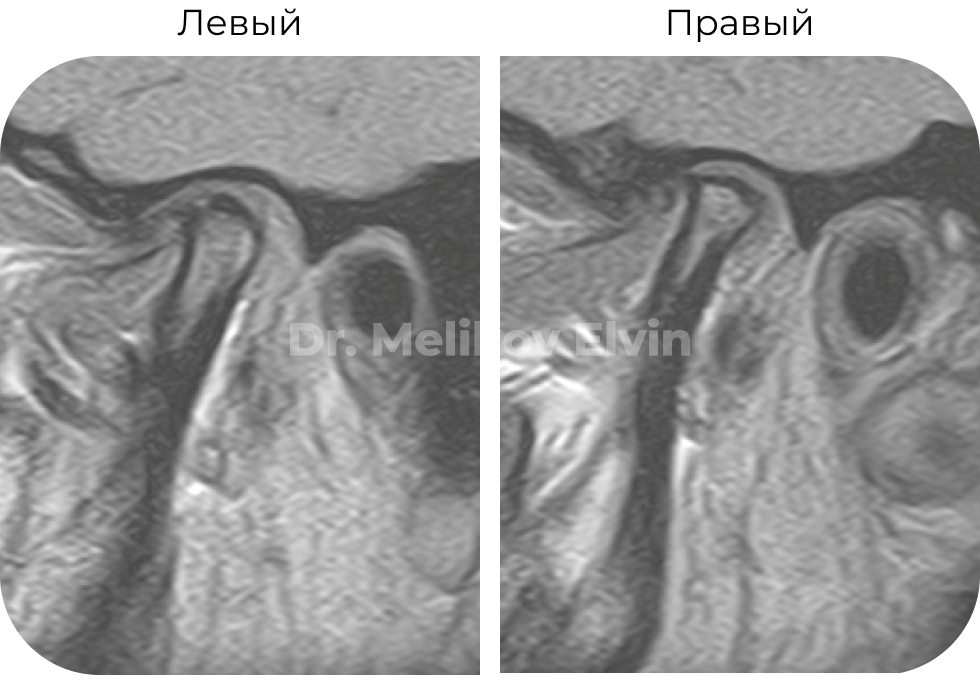

Магнитно-резонансная томография до лечения. Заключение:

МР-картина артроза ВНЧС 2 стадии (больше справа), умеренного синовита справа.

В положении привычной окклюзии отмечается вентромедиальная дислокация суставного диска справа, медиальная — слева.

При открывании рта отмечаются признаки гипермобильности ВНЧС слева, с передним смещением суставного диска справа.

Функциональная перегрузка латеральных крыловидных мышц.